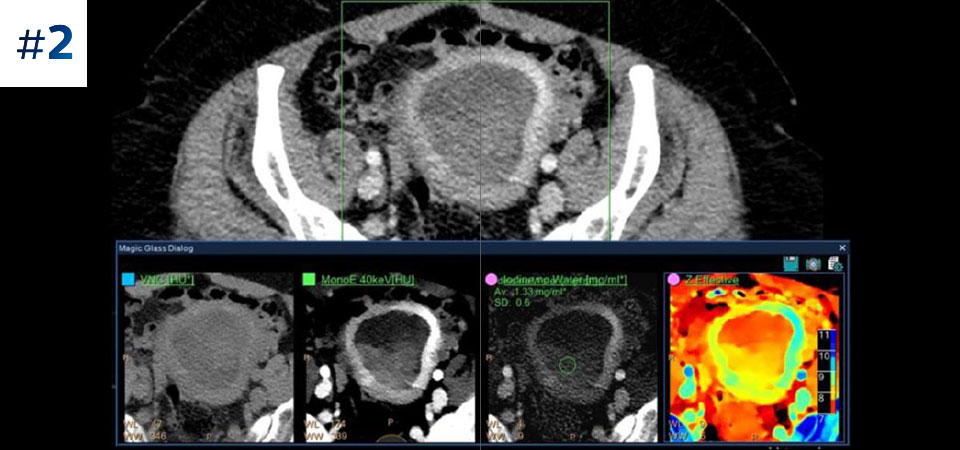

Pacjenci o różnych typach budowy ciała Możliwość przeprowadzania badań u pacjentów różnej wielkości, od dzieci po osoby otyłe.

Ograniczenie liczby ponownych badań Udoskonalona charakterystyka i wizualizacja tkanek może ograniczyć konieczność wykonywania ponownych badań, jaka zachodzi w przypadku badań o niezadowalającej jakości oraz przypadkowych obserwacji.

Nie ograniczaj się do konwencjonalnej tomografii komputerowej. Zobacz, jak wyniki uzyskane dzięki warstwom detektora spektralnego mogą zwiększyć pewność diagnostyczną.

Zobacz jak tomograf spektralny pomaga w diagnostyce pacjentów onkologicznych.